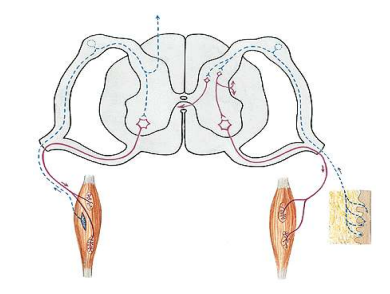

Rückenmark

Nervengeflechte

Nervenbahnen in grauersubstanz führen zum Gehirn und tretten unten wieder aus, dementsprechend der Funktion

Hinterhorn: sensible Fasern → Spüren, sensorisch

Vorderhorn: motorische Fasern → Bewegung, Ansteuerung Muskulatur